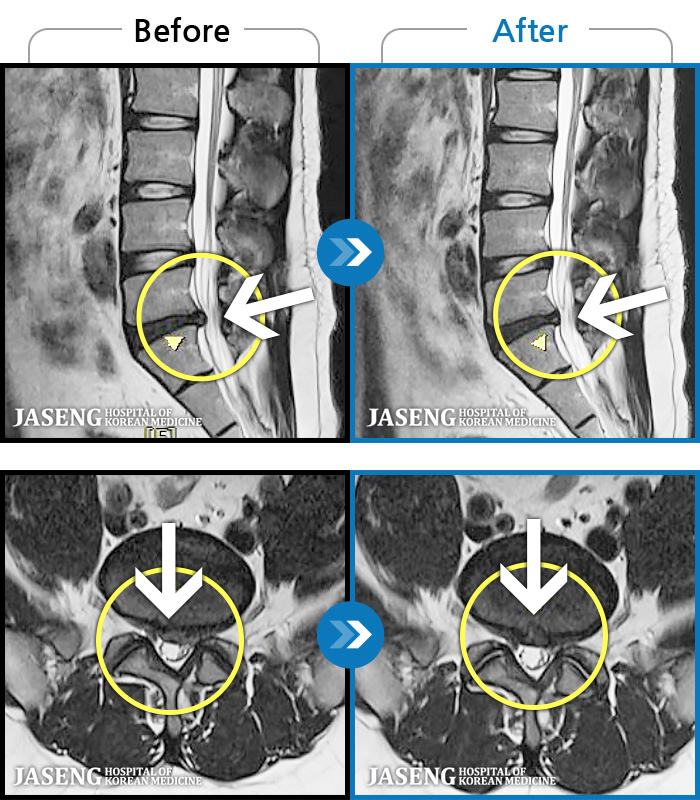

MRI ġ

1,243 MRI ũ ʸ Ȯϼ.